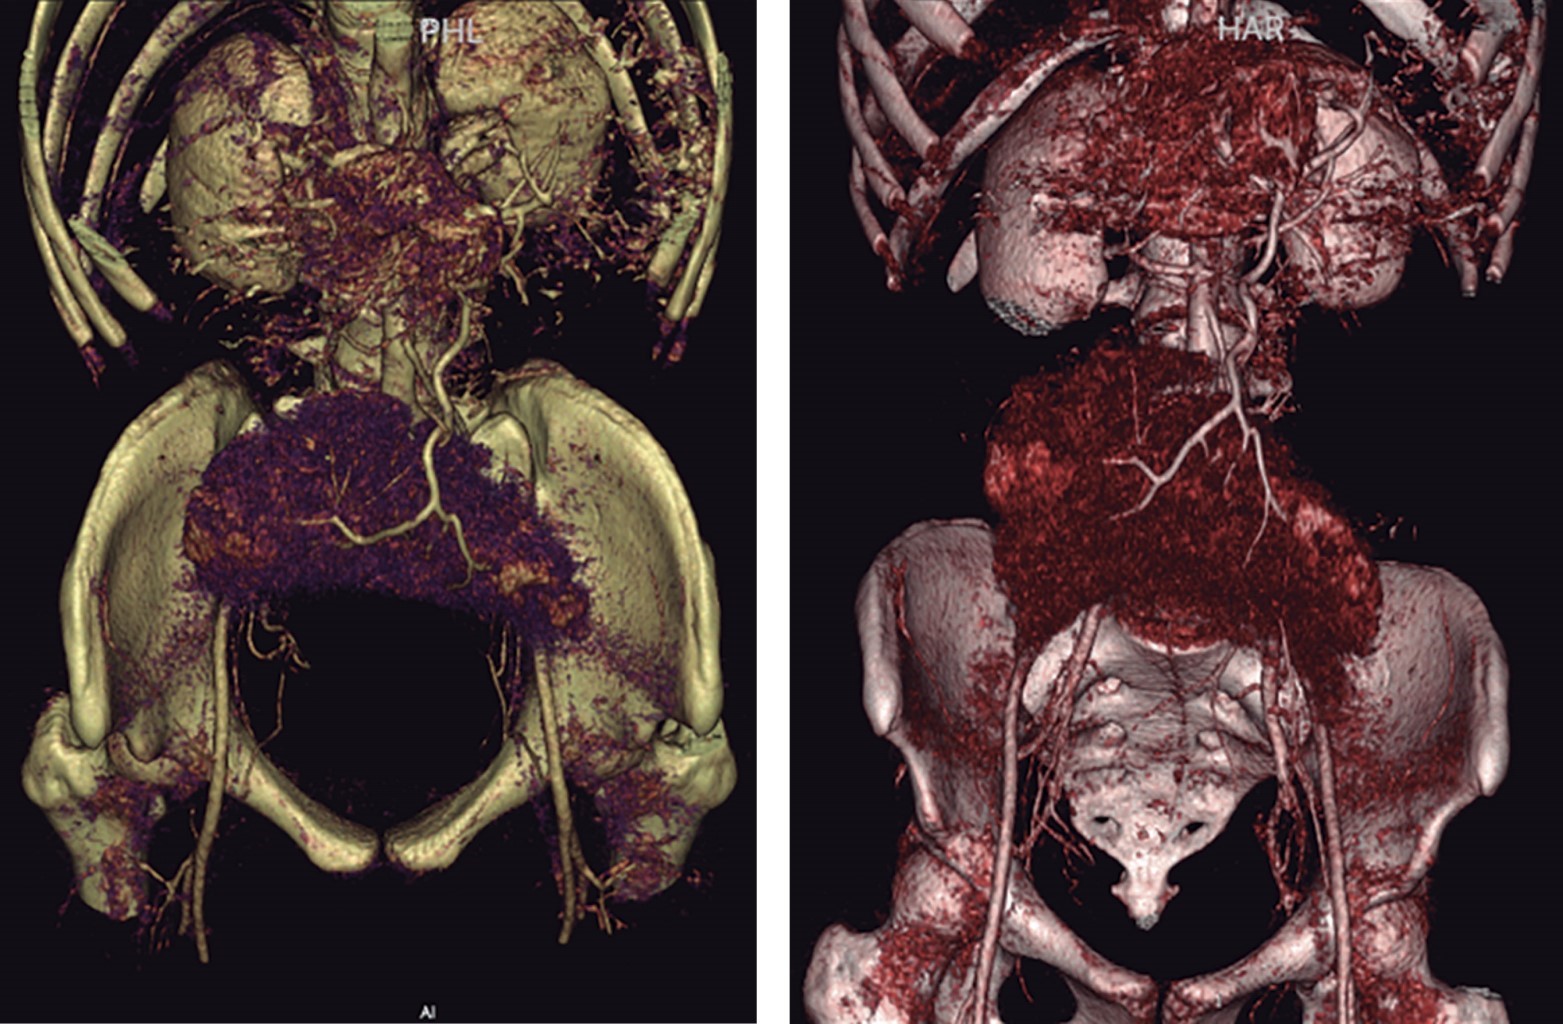

A la exploración física se logra palpar tumor delimitado, móvil, de aproximadamente 9 × 8 cm en cuadrante inferior izquierdo, sin datos de irritación peritoneal, se complementa abordaje con laboratorios en los que se reporta biometría hemática y química sanguínea dentro de parámetros normales, Ca-125 17 U/ml, tomografía abdominopélvica que reporta imagen compleja dependiente de ovario izquierdo (Figuras 1 y 2). Se decide realizar laparotomía exploradora electiva, donde se encuentra presencia de bazo errante a nivel pélvico con quiste de 9 × 9 cm (Figuras 3, 4 a 5), se realiza evisceración de bazo y drenaje de quiste, obteniendo 480 cm3 de contenido cetrino. Se solicita apoyo transoperatorio al Servicio de Cirugía General para la realización de esplenectomía, la cual se lleva a cabo con éxito. Útero, anexos y resto de vísceras sin alteraciones. Evolución postoperatoria adecuada, con egreso a las 24 horas de su ingreso, continuando con protocolo de paciente postesplenectomizado por externo.

El cuadro clínico cuando se presenta sintomático suele ser inespecífico, por lo que los estudios imagenológicos juegan un importante papel en el diagnóstico y de sus complicaciones. La tomografía abdominal contrastada es considerada el mejor estudio, aunque también pudiera ser útil el ultrasonido de abdomen. A menudo se identifica por su forma característica de "coma", sin observar el bazo en el cuadrante superior izquierdo; seguir el trayecto de los vasos esplénicos puede ayudar a identificar correctamente el bazo errante (Figuras 2 y 7).2

AGRADECIMIENTOS